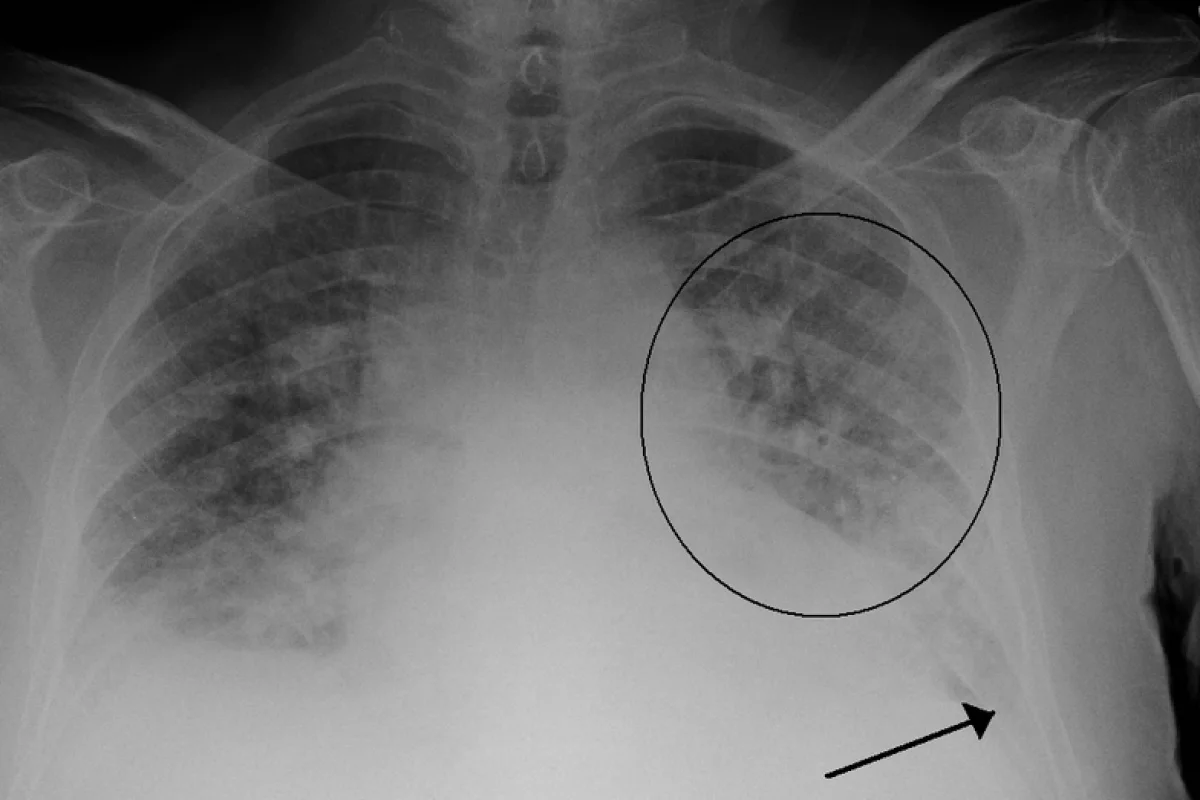

A new machine learning algorithm was shown to be capable of classifying severe cases of pulmonary edema with high accuracy

In putting it to the test, the team had the machine learning algorithm analyze single X-ray images and classify the severity of edema, ranging from 0 (healthy) to 3 (very, very bad). The algorithm was able to diagnose the correct level of edema more than half the time, but more impressively, was able to accurately diagnose level-3 cases 90 percent of the time.